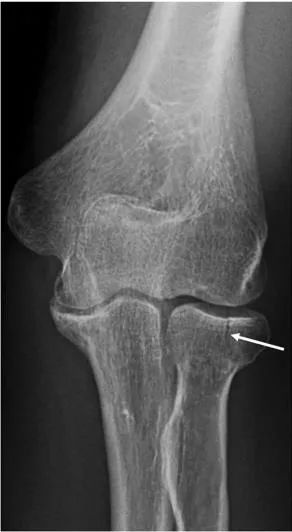

I 型骨折(图8)是无移位或轻微移位(<2 mm)骨折。

图8 桡骨头骨折。41岁女性肘关节正位片显示轻度移位桡骨头骨折(Mason-Johnston分类中的I型骨折)